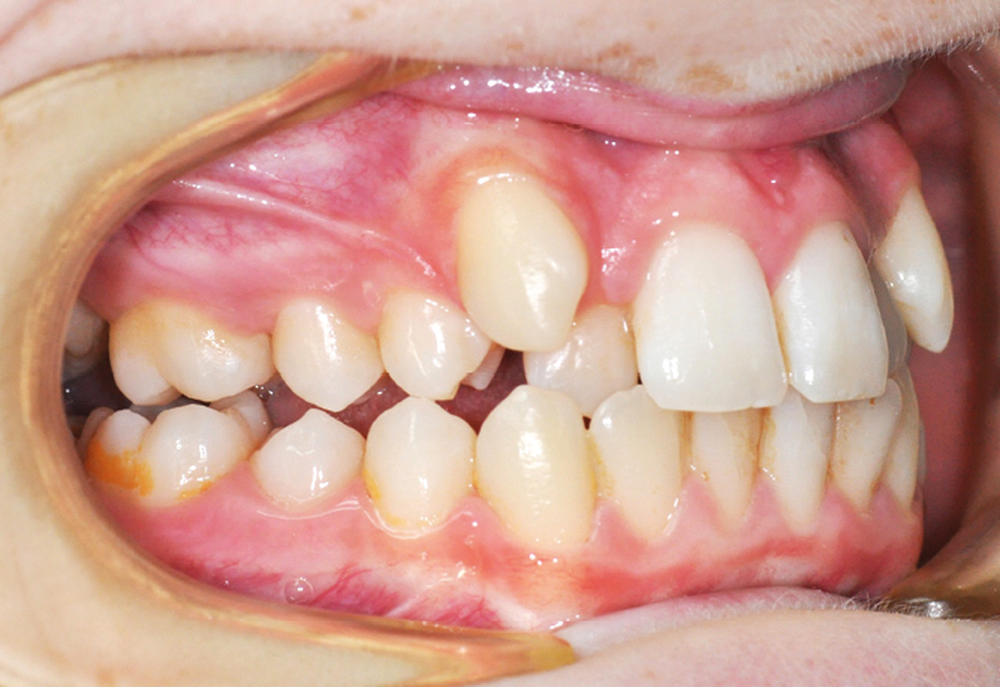

Julien nous consulte à l’âge de 11 ans et 4 mois pour des raisons essentiellement esthétiques, afin d’améliorer l’alignement de ses incisives maxillaires (fig. 1a-d) ; son chirurgien-dentiste l’a toutefois alerté sur un problème d’évolution des 35 et 47, dont l’inclusion a été mise en évidence lors d’un contrôle radiographique (fig. 1e).

Le patient présente des lèvres fines et un profil orthofrontal avec des pommettes effacées. Le sourire est inesthétique du fait de l’encombrement maxillaire, mais aussi en raison de la contraction asymétrique de la lèvre inférieure.

L’examen intra-oral met en évidence une occlusion inversée bilatérale ainsi qu’un manque de place conséquent pour les incisives latérales maxillaires en palato-position et une infra-vestibulo-position de 13 et 23. Le patient est déjà en denture adulte jeune, hormis la persistance de la 75. L’occlusion est en classe II, plus marquée du côté droit sans engendrer de déviation des médianes incisives, d’où une mésio-position plus importante de la 13 par rapport à la 23.